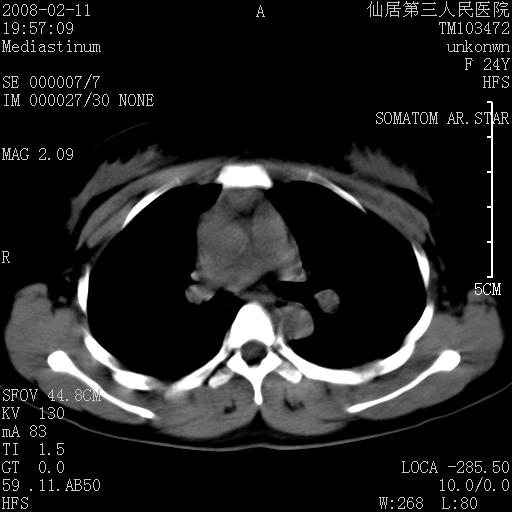

以下是引用zjzjr在2008-2-12 14:32:00的发言:[br]胸腺大点,是不是胸腺瘤或胸腺增生